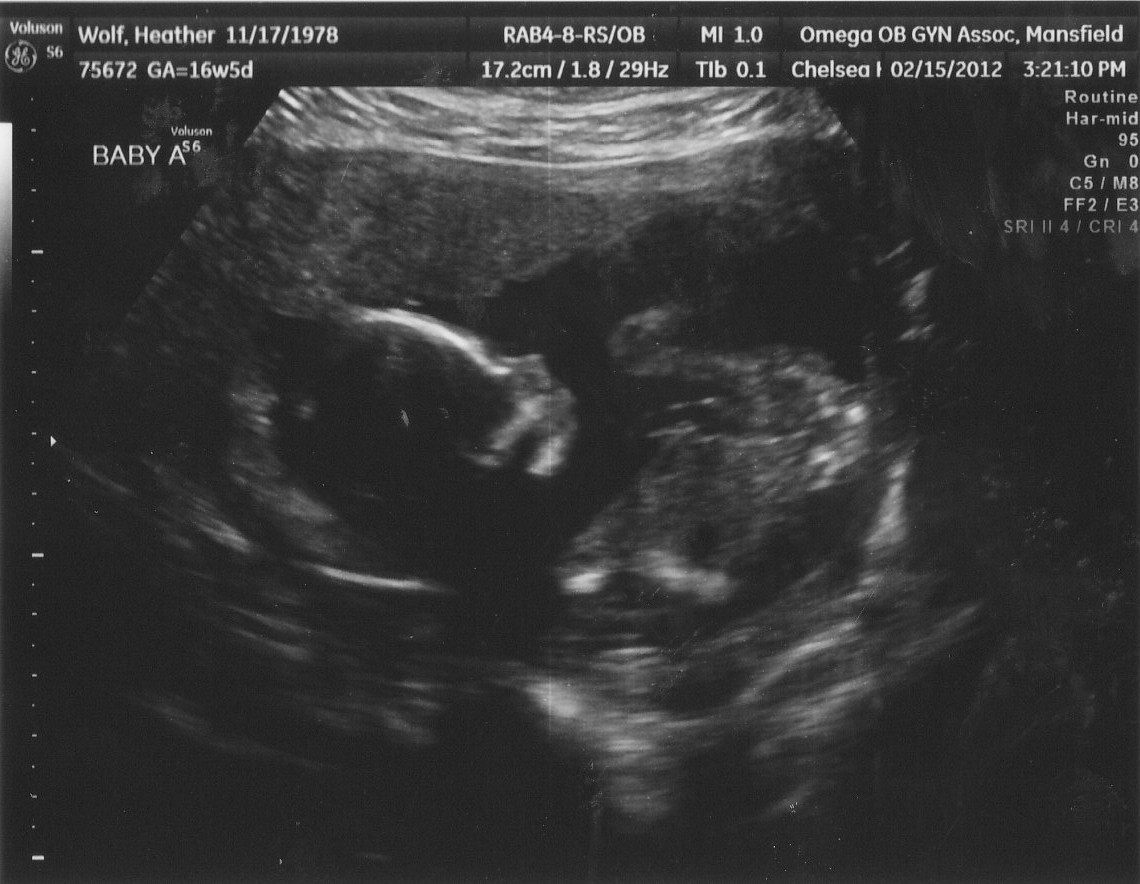

| They're getting big enough that they don't fit one screen together - although we got a quick shot here. (I think a head and a behind with legs but not 100% sure) |